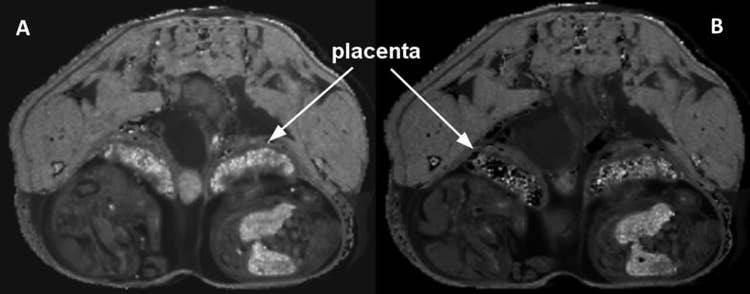

MRI Mouse gestation slice